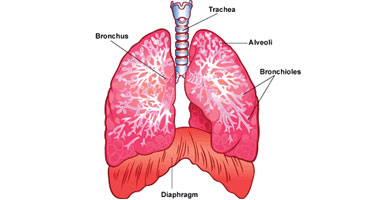

قصبة هوائية ويكيبيديا

جهاز تنفسي ويكيبيديا

ما وظيفة الرئتين بجسم الإنسان اليوم السابع

وظائف الرئتين الرئة البشرية البنية الوظيفة الدواء 2020

أين تقع الرئتين في جسم الإنسان موضوع